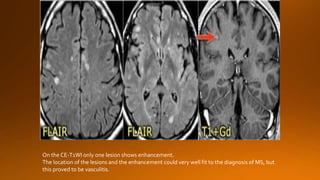

On the CE-T1WI only one lesion shows enhancement.

The location of the lesions and the enhancement could very well fit to the diagnosis of MS, but

this proved to be vasculitis.